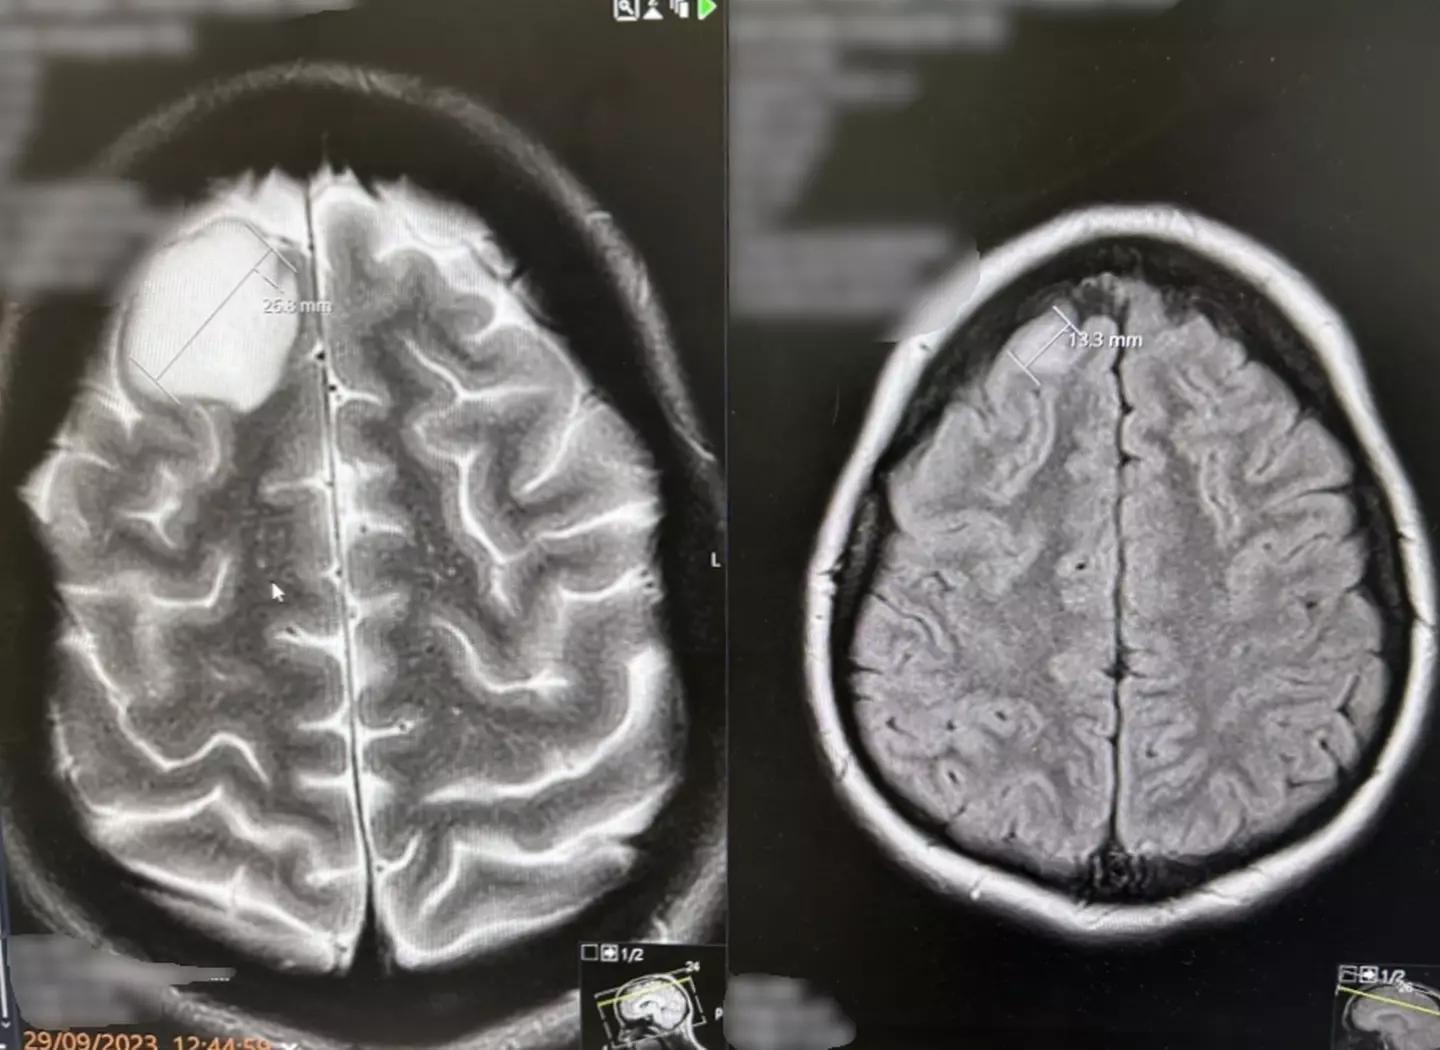

An MRI scan revealed she had an incurable brain tumour growing in her head, but was told she couldn’t begin treatment until her baby arrived.

However, after she began experiencing debilitating headaches again, doctors referred her for surgery, and she underwent a five-hour craniotomy operation to remove the brain tumour from the frontal lesion on 14 February.